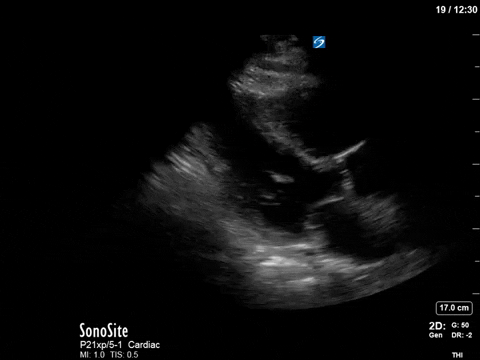

Here’s a clip from the initial cardiac POCUS:

In this case, the tracing is imperfect as the A5C image was challenging and varied with respiration. Nevertheless, we can clearly see aliased signal that is unmeasurable with PW.

This is one of the general advantages of spectral doppler – in cases where the 2D images are not ideal and difficult to interpret, the spectral tracing is often more “forgiving” and you can still obtain valuable information.